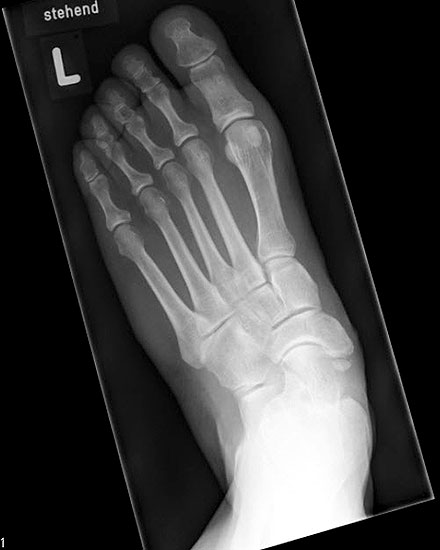

Stehende konventionelle Röntgenbilder eines Fußes mit Planovalgus Deformität Stadium II b dorsoplantar (dp) und seitlich. Auf der dp-Aufnahme zeigt sich die talo-calcaneare Divergenz, der gegenüber dem Kalkaneus nach anterior gleitende Talus und d

Abbildung 5

Stehende Aufnahmen des Fußes dorsoplantar (dp) und seitlich sowie des OSG anteroposterior (ap) sind die Grundlage der konventionellen Röntgendiagnostik (Abb. 5). Ergänzend werden gelegentlich die Rückfuβ-Alignement Aufnahme nach Saltzman 19 und Vergleichsaufnahmen der Gegenseite durchgeführt.

Der Talo-Metatarsale I Winkel bzw. die laterale talonaviculare Subluxation auf der stehenden dorsoplantaren Aufnahme des Fuβes dokumentieren das Ausmaβ des Vorfuβ abductus (Abb. 6 a,b). Ein dp Talo-Metatarsale I Winkel von > 10° (nach medial konvex) ist als pathologisch anzusehen. Mit der Bestimmung der talocalcanearen Divergenz (Abb. 6 c) erhält man ein Eindruck über das Ausmaβ des Rückfuβ valgus; eine leichte Divergenz bis ca. 12° gilt als physiologisch 20.